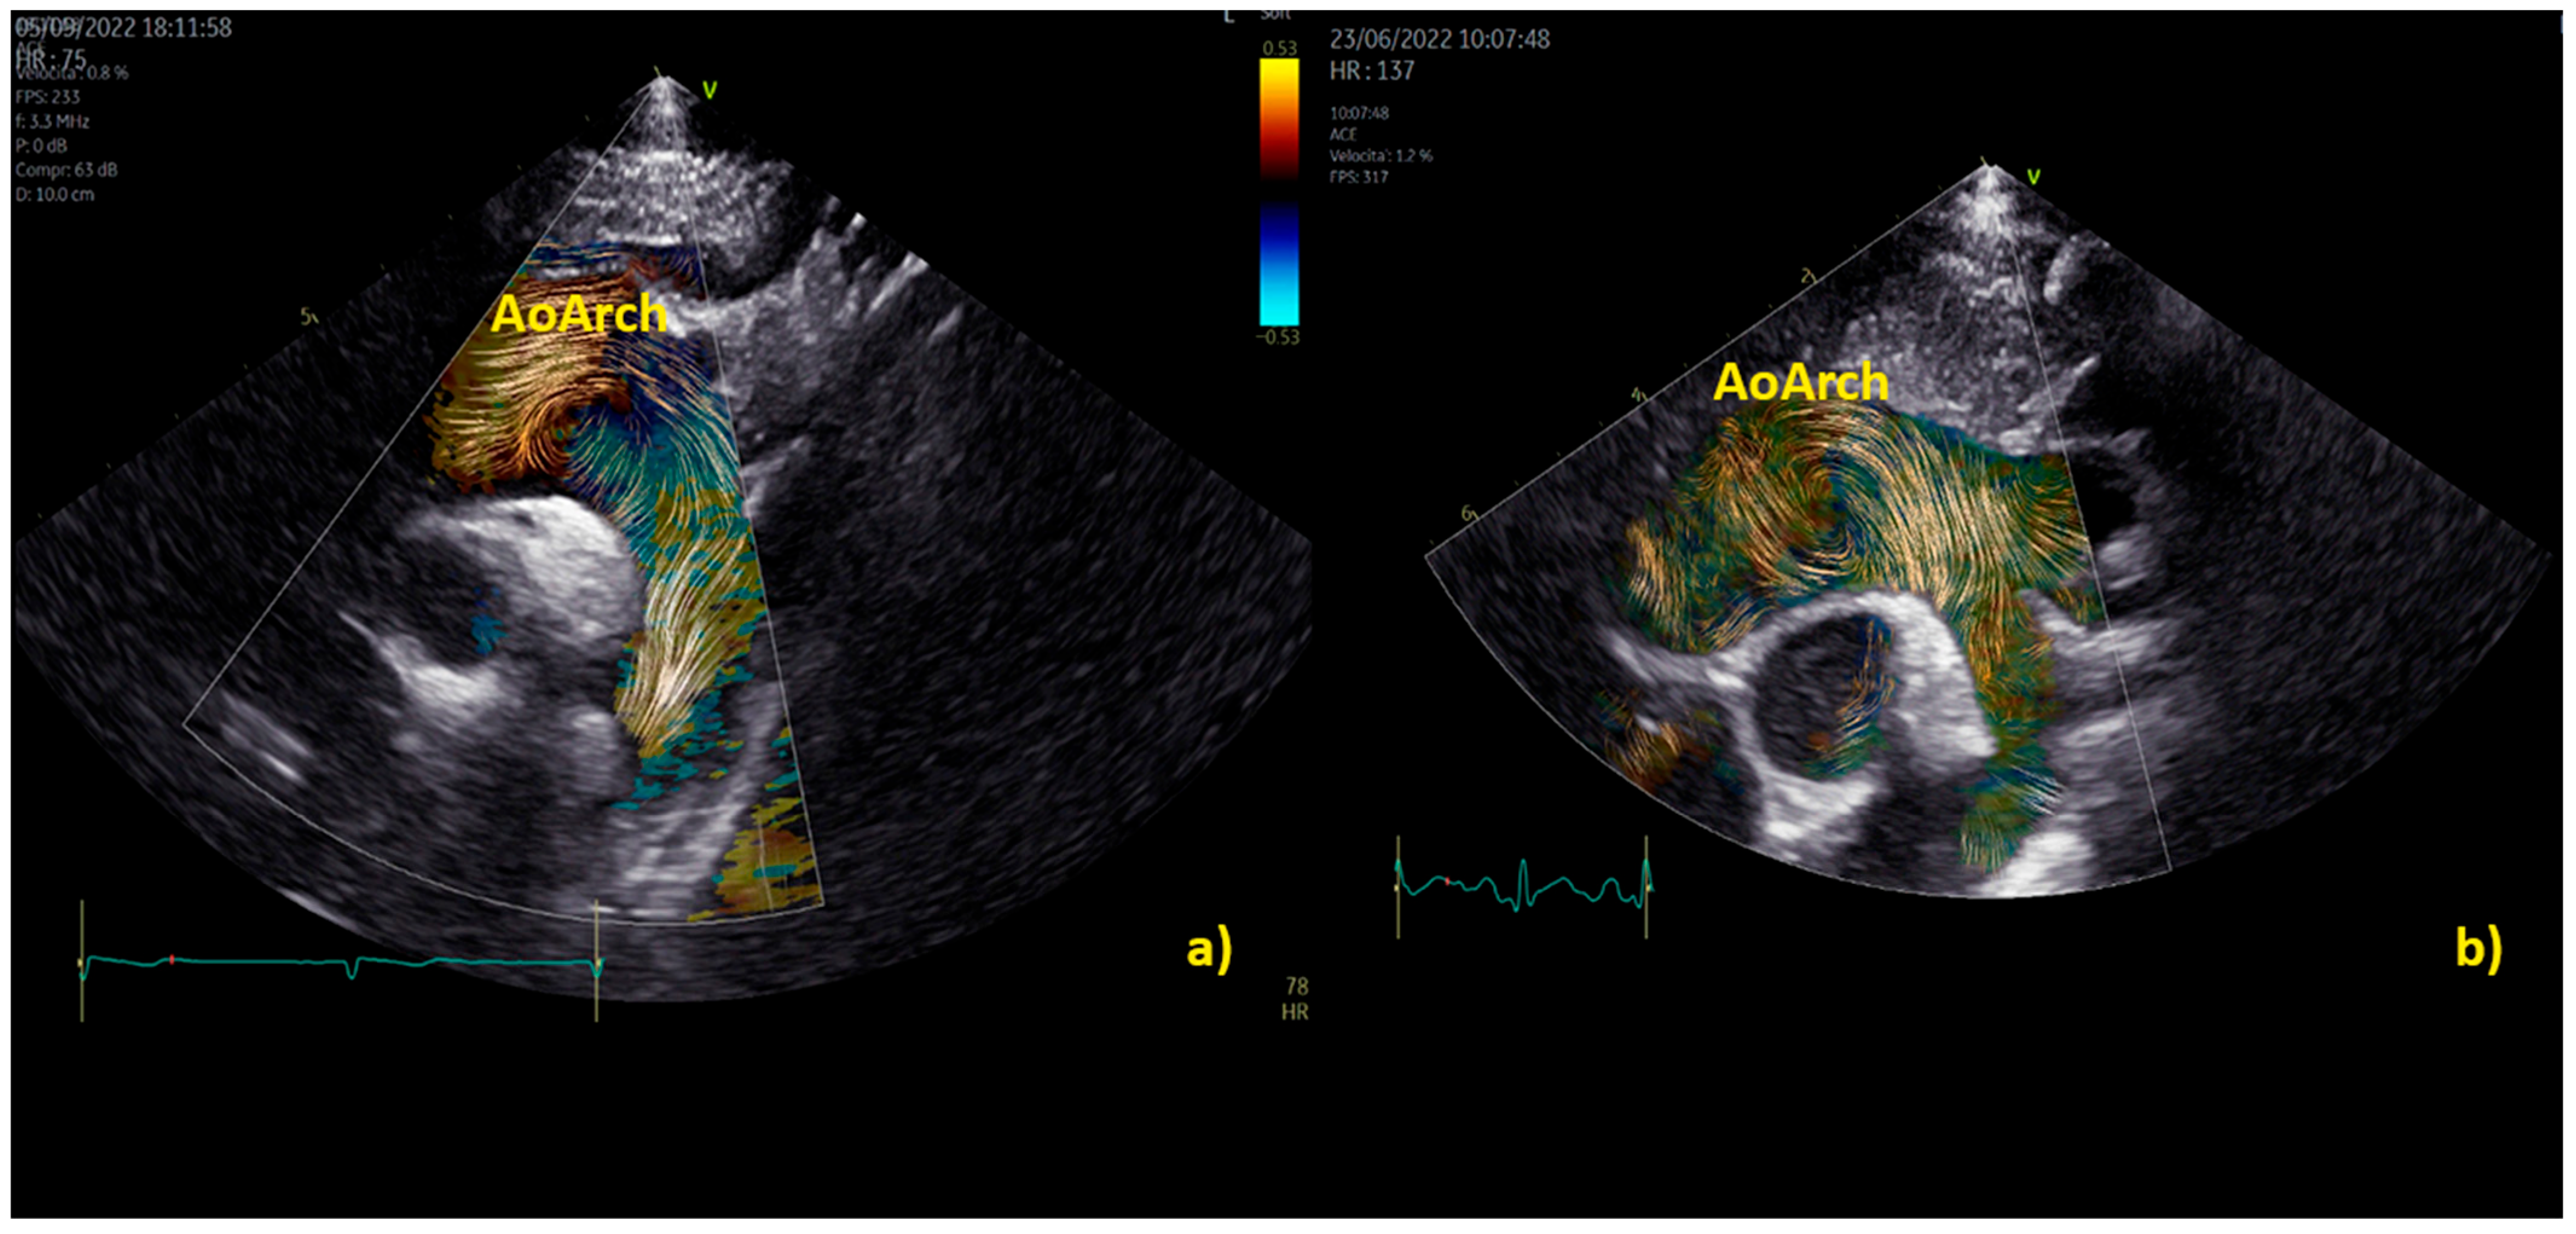

Practical examples of differences among physiological and pathological aortic vortices are provided in Figure 5. In Figure 5a, a physiological vortex is shown, while in Figure 5b, an example of a big vortex in the dilated ascending aorta of a child with a bicuspid aortic valve with moderate stenosis has been provided. The propagation of the vortex in the aortic arch in physiological condition and in a child with bicuspid aortic valve with moderate stenosis is shown in Figure 6. In the example, it appears clear that the vortex of the healthy patient (Figure 6a) occupies a smaller area than the pathological vortex and is localized on the ventral surface of the aortic arch, below the first two epi-aortic branches. On the contrary, the vortex of the child with bicuspid aortic valve valvular stenosis (Figure 6b) is located proximal to the epi-aortic branches and occupies the great part of a dilated transverse arch.

Figure 6. Vortex in the aortic arch in a healthy child (a) and in a 3-year-old child with moderate aortic valve stenosis (b). It appears clear that the vortex of the healthy patient (a) occupies a smaller area than the pathological vortex and is localized on the ventral surface of the aortic arch, below the first two epi-aortic branches; on the contrary, the vortex of the child with valvular stenosis (b) is located proximal to the epi-aortic branches and occupies the great part of a dilated transverse arch.